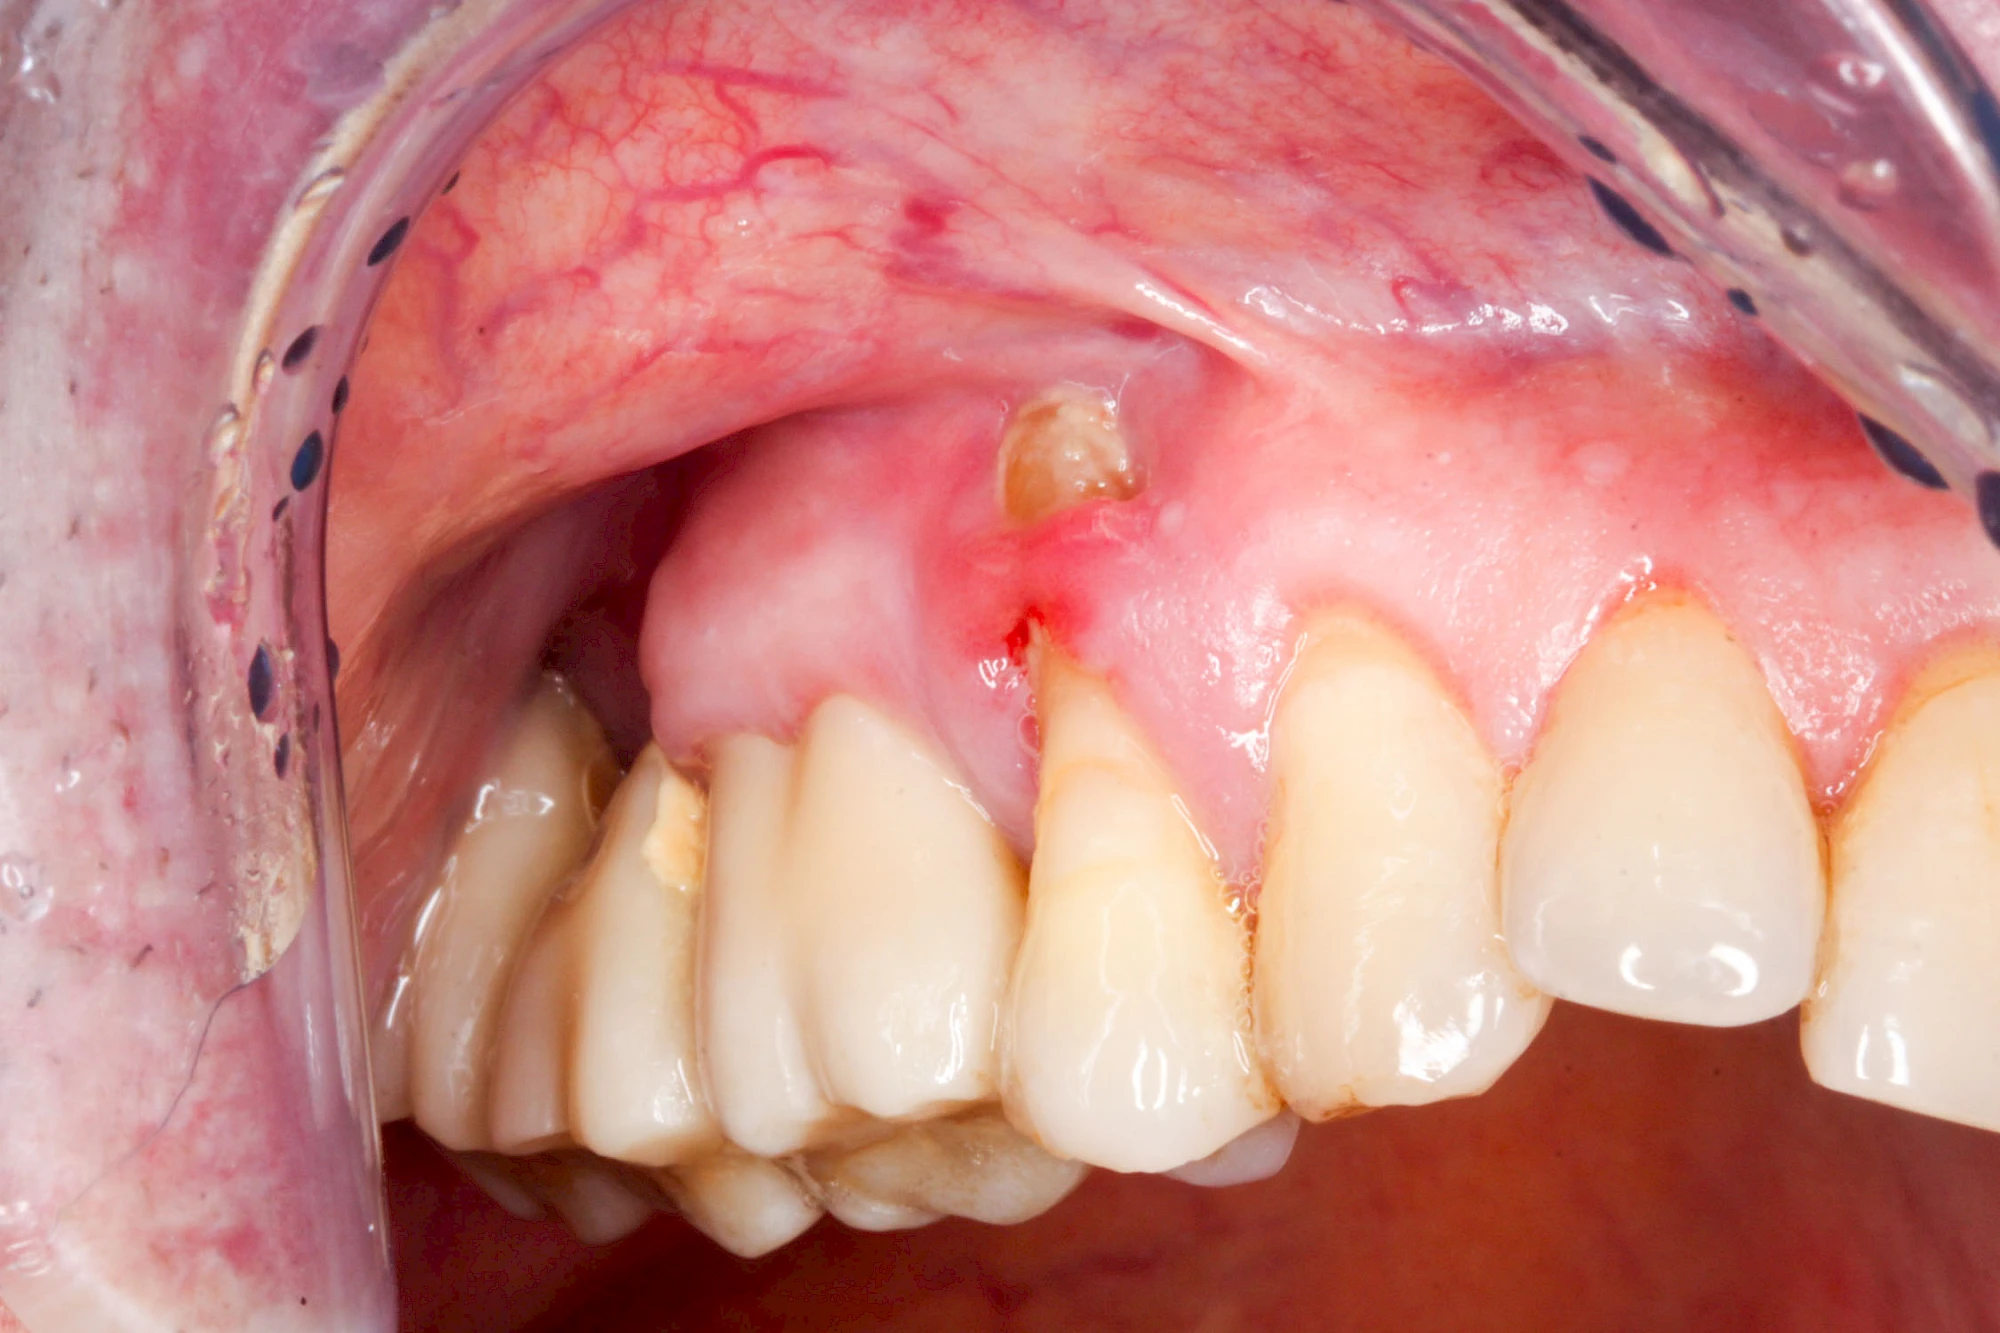

Sonderform: Fistel

Bei einer Fistel hat sich meist eine Entzündung (manchmal auch Erreger selbst) z. B. aufgrund von Karies oder aufgrund eines Unfalls über den Zahnnerv und die Wurzelspitze (Apex) in den umliegenden Knochen ausgebreitet (apikale Parodontitis) und schnell einen Weg durch den umgebenden Knochen und die aufliegende Schleimhaut in die Mundhöhle gebahnt.

Fisteln sind in der Regel nicht schmerzhaft und fallen häufig als kleine Öffnung weiter entfernt vom Zahnfleisch nahe der Umschlagfalte auf. Aus der Fistelöffnung entleert sich spontan gelbliches Sekret (Eiter) oder es lässt sich mit dem Finger ausstreichen. Manchmal beschreiben die betroffenen Menschen immer wieder einen komischen Geschmack im Mund.

Im fortgeschrittenen Stadium kann die Schleimhaut sich weiter zurückgezogen haben und die Wurzelspitze sichtbar sein. In der Regel treten bei Fisteln keine Schwellungen auf, weil sich die Entzündung nicht im Gewebe ausbreitet.

Bei Fisteln sollte zeitnah der Zahnarzt kontaktiert werden. Treten Fisteln im Zusammenhang mit Schwellungen auf, ist sofort der Zahnarzt zu kontaktieren. Ist der Zahnarzt nicht zu erreichen und es verschlechtert sich der Allgemeinzustand (z. B. Fieber) sollte der Notarzt gerufen werden.